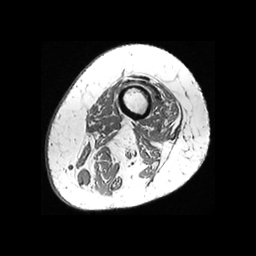

Finally, we define the set of corrected pseudo-labels as the intersection between the and masks. Examples are shown in Fig. 2.

(a) Image

(b)

(c)

(d)